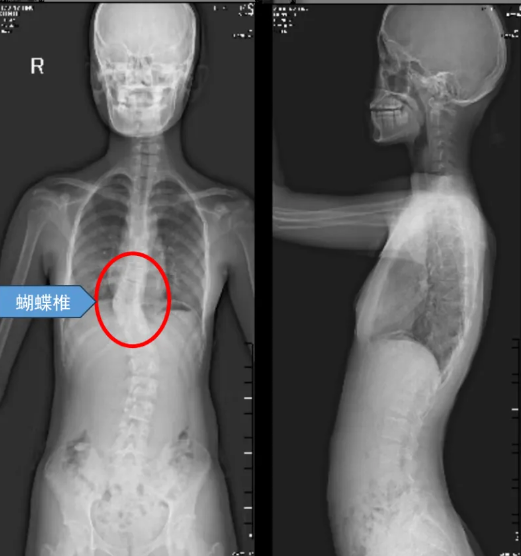

近日,广东医附院脊柱退变与畸形外科在副院长林颢教授和科主任魏劲松教授的带领下成功完成了粤西首例先天性蝴蝶椎经后路全椎体切除矫形内固定术(VCR)为一名年仅13岁的少女重新挺直了脊梁开启了她人生新的篇章

蝴蝶椎,这美丽的名字背后,却隐藏着无尽的痛苦与挑战。蝴蝶椎畸形,作为一种罕见的先天性脊柱畸形,也被称为矢状椎体裂,其发病原因是胚胎发育期间脊柱椎体的两个软骨中心在发育过程中未能正常融合,导致椎体成为左右对称的两个三角形骨块,形似蝴蝶的双翼,故得名蝴蝶椎。蝴蝶椎畸形并不一定需要手术,但在某些情况下,如多发蝴蝶椎或蝴蝶椎发育高度不平衡时,可能导致脊柱侧凸、后凸等脊柱畸形及疼痛、活动能力下降、心肺功能障碍等,就需要尽早手术干预了。

家在遂溪的13岁女孩小亭,患的就是这样一种疾病。而且由于该蝴蝶椎前后发育不平衡,导致小婷脊柱明显畸形,长期遭受着侧弯和驼背的折磨,不仅身体形态不美观,而且运动能力也大幅下降,跑几步就气喘吁吁,心理上更是承受着巨大的压力。家人焦急万分,四处打听,方才得知小亭这种病需要做手术,但是该手术难度高,风险大,不禁又犯了难,到底该不该做手术?要到哪里做?

8月23日,医院手术室内气氛紧张而凝重。魏劲松教授凭借其深厚的学术造诣和丰富的临床经验,带领团队全力以赴,每一个细节都力求完美。经过数小时的精细操作,手术顺利完成,不仅成功切除了畸形的蝴蝶椎,还通过相对短的节段固定重建了脊柱的稳定性,矫正了原有的畸形。